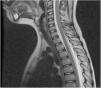

CSF hypotension arises in the context of a leak of CSF which causes negative intracranial pressure. Sacral fractures result from high-energy trauma which are frequently underdiagnosed. A ten-year-old boy presented with hip pain, after a fall. He mobilized both lower limbs, reported no leg pain, irradiation nor lack of sphincter control. The neurological examination was normal. When asked to stand, he began biparietal headache, nausea and vomiting, which improved laying down. CT scan showed an occult intrasacral meningocele; the MRI revealed collections of CSF along the spine, a S3 fracture with potential laceration of the meningocele and opening of a CSF fistula. Our diagnosis was the CSF hypotension, secondary to the fistula opening. The diagnosis was challenging. The child first presented with symptoms of CSF hypotension without evident cause. The discovery of the meningocele led us to hypothesize the opening of a fistula, a rare diagnosis, later confirmed by MRI.